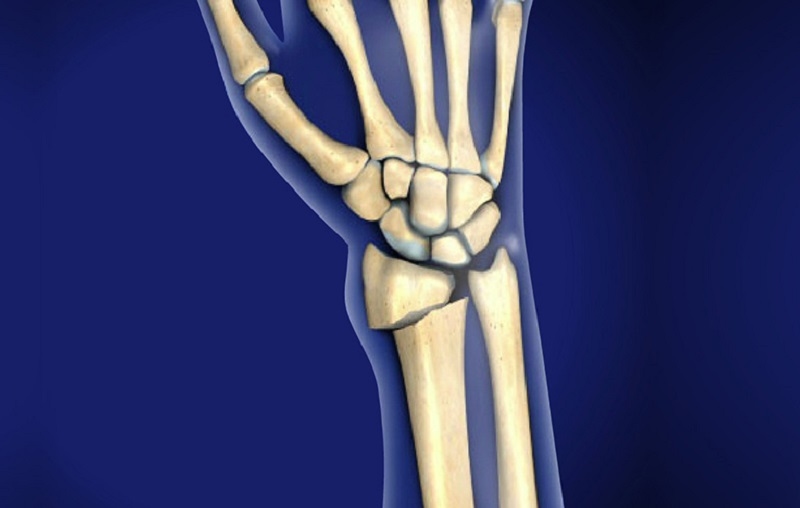

Cổ tay là một cấu trúc phức tạp, gồm 8 xương nhỏ có hình dạng khác nhau như hình vuông, hình bầu dục và hình tam giác, liên kết với hai xương dài của cẳng tay là xương quay và xương trụ. Kỹ thuật chụp X – quang cổ tay giúp hiển thị rõ cấu trúc giải phẫu này thông qua hình ảnh với các sắc độ xám khác nhau.